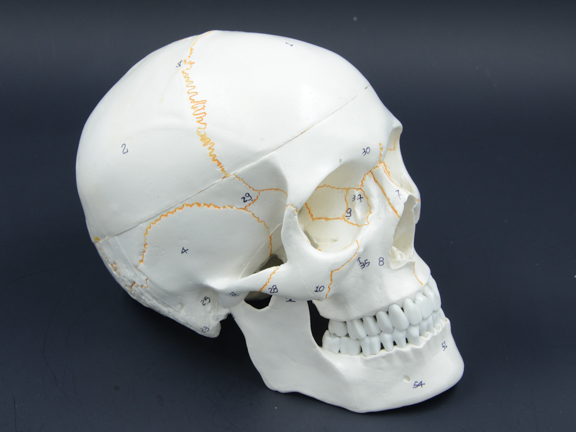

К скелету нижней части относят тазовую и бедренные кости, надколенники, большеберцовую кость, малоберцовую кость, а также кость стопы. В основном большинство травм связанных с костями происходит именно с скелетами верхней и нижней частей. Это вполне объяснимо, так как эти скелеты наиболее активно участвуют в передвижении человека, и они чаще всего подвергаются воздействию со стороны. Реже, но все равно бывают различные травмы черепа. Сам череп представлен на рисунке ниже:

Рис. 2.4. Череп

Как можно увидеть череп состоит их решетчатой кости, лобной кости, теменной кости, слезной кости, носовой кости, затылочной кости, височной кости, скуловой кости, нижней челюсти, верхней челюсти, а также клиновидной кости. Так как подвижной частью в черепе является нижняя челюсть, то с ней наиболее часто случаются различные травмы, которые могут серьезно сказаться на здоровье человека. Обычно травмы нижней челюсти случаются при ударах. Интересен и тот факт, что все кости черепа соединены между собой с помощью зубчатых швов. Эти швы помогают наиболее плотно скрепить черепные кости.

Череп: анатомия сложнейшей части скелета человека

Строение и функции головы занимают одну из ключевых позиций в изучении медицины, и небезосновательно: именно в черепе заключены основные органы, благодаря которым человек способен воспринимать и понимать окружающий мир, поддерживать большинство физиологических функций и формировать сознание. Важнейшую роль здесь играет головной мозг – именно его так усиленно защищают кости черепа, стараясь предотвратить малейшую травму, которая может быть чревата серьёзными последствиями.